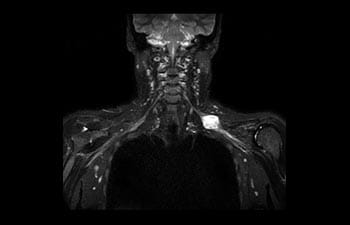

Conozca cómo Ingenia Prodiva puede satisfacer sus necesidades clínicas.

Conozca la opinión de los primeros usuarios de Ingenia Prodiva 1.5T acerca de sus experiencias con el sistema y cómo influye este en su centro de diagnóstico por imagen.